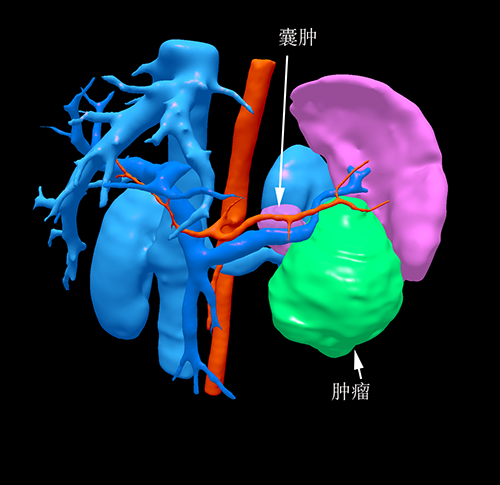

胰体尾实性假乳头状瘤---腹腔镜胰体脾切除